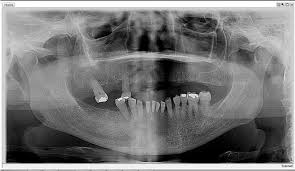

Silent Sinus Syndrome An Imploding Antrum Syndrome Choudhary Sh Kale L Mishra Ss Choudhary Ak J Indian Acad Oral Med Radiol

Silent Sinus Syndrome Report Of A Case Oral Surgery Oral Medicine Oral Pathology Oral Radiology And Endodontics

Silent Sinus Syndrome Interesting Clinical And Radiologic Findings Journal Of Oral And Maxillofacial Surgery